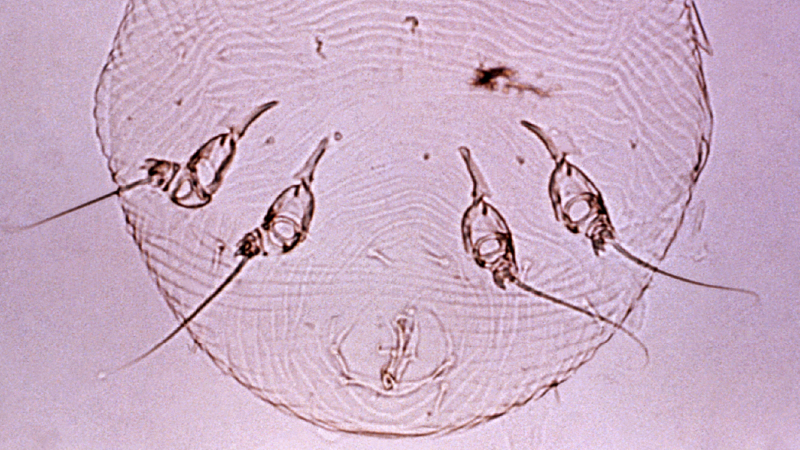

La scabbia è un’infestazione parassitaria cutanea causata dell’acaro Sarcoptes scabiei che si insinua nella pelle causando intenso prurito e lesioni cutanee. La femmina del parassita depone le uova creando delle piccole tane a forma di serpentina.

La diagnosi è clinica, basata sulla sintomatologia e l’osservazione diretta della cute. A volte possono essere eseguiti alcuni test microscopici di approfondimento.